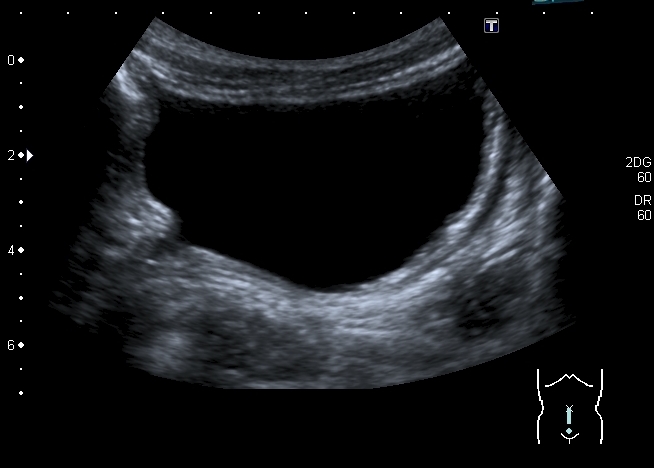

Мочевой пузырь:

Определяется небольшое расширение лоханок обеих почек, стенки их гиперэхогенные, утолщены.

"Маленькие белые почки" с расширением ЧЛС и мочеточников, умеренной латерализацией устьев, без видимых на высокочастотном УЗИ кист. Печень без видимых на высокочастотном УЗИ кист. Опухоль слева.